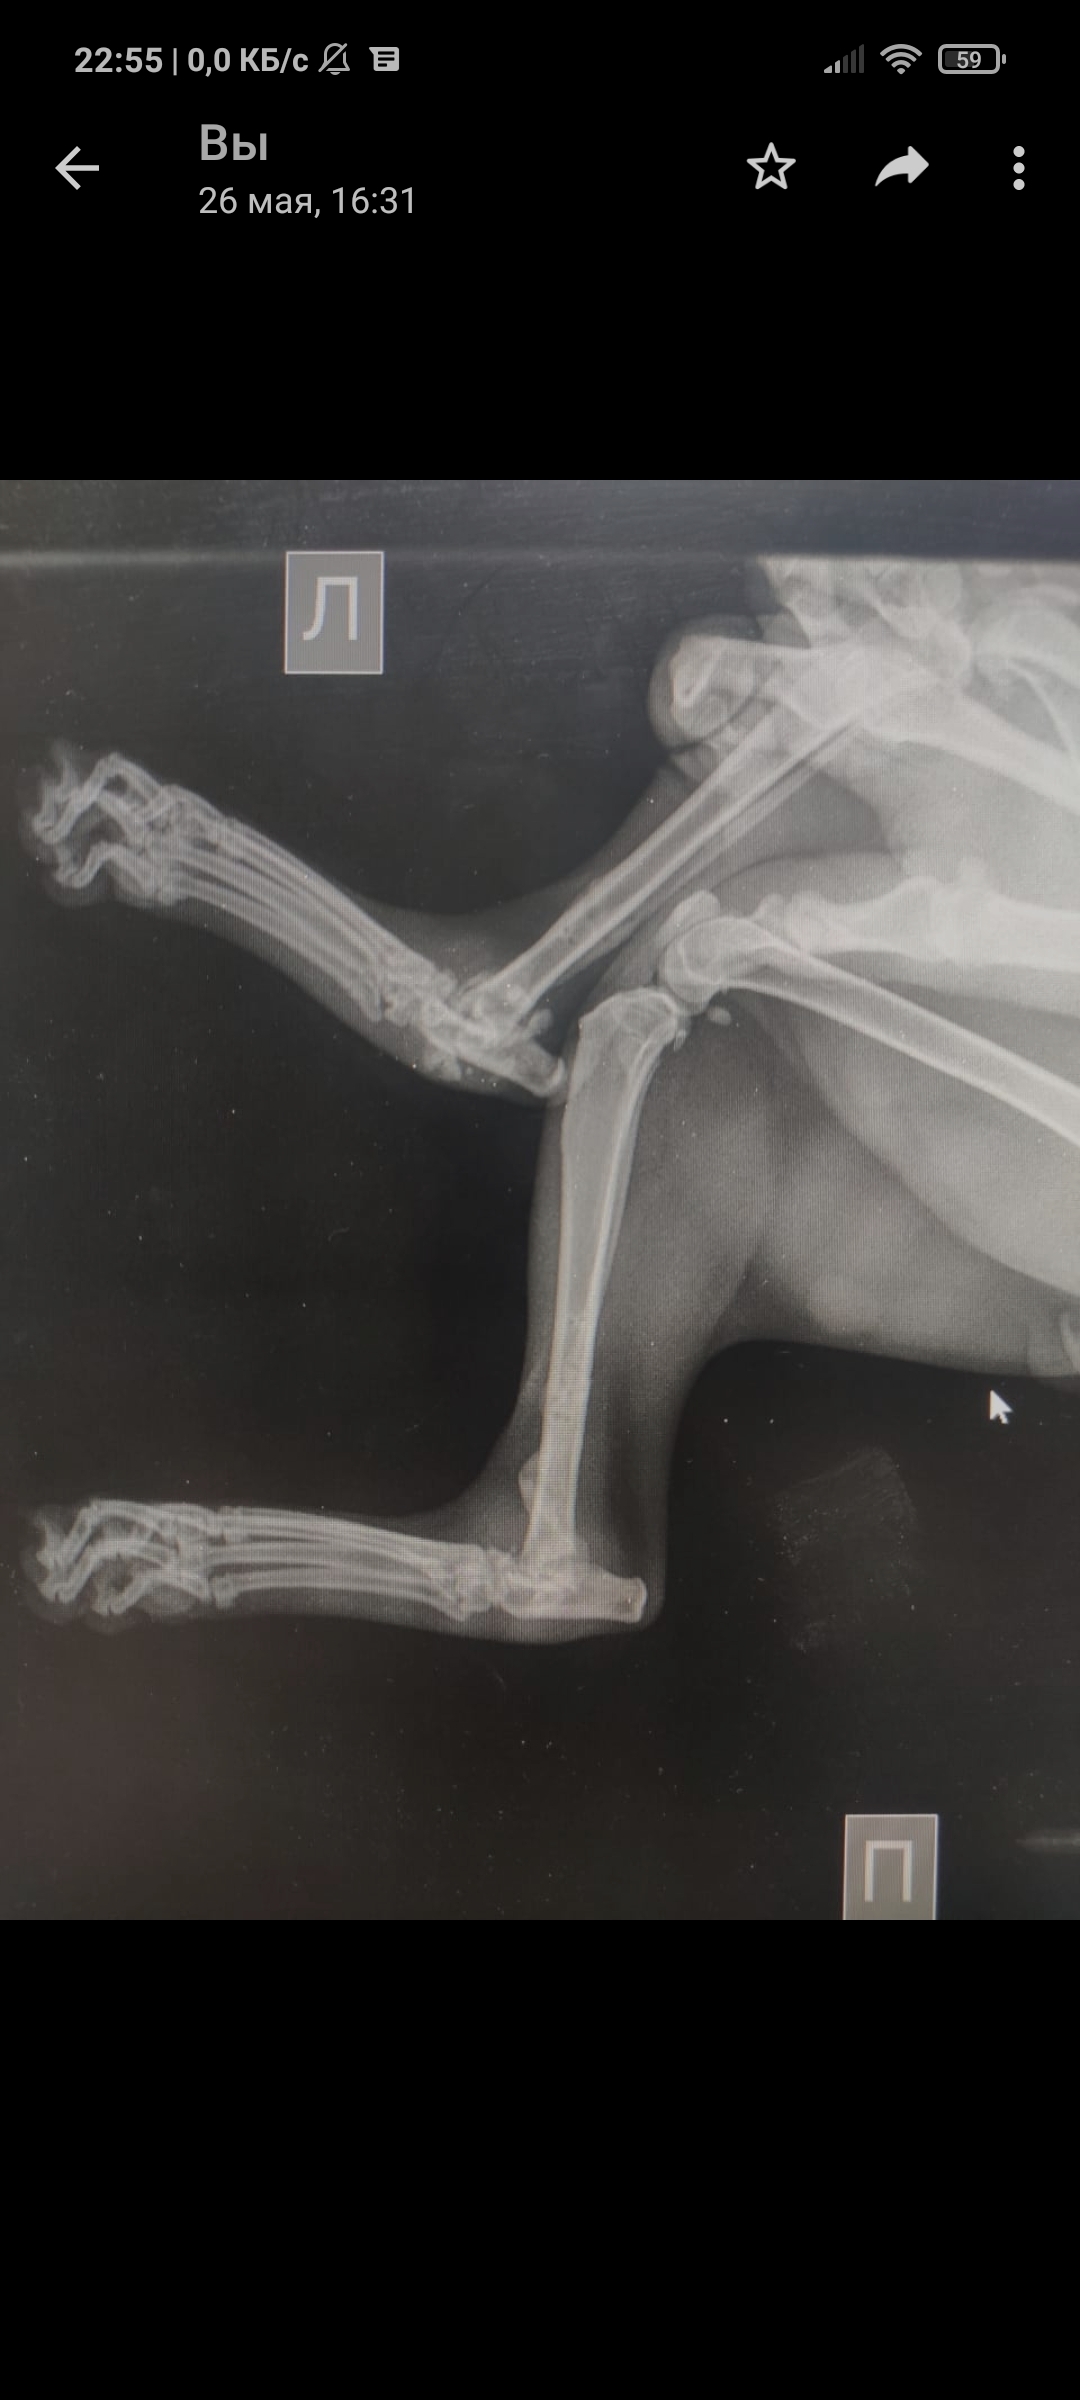

Так уж получилось что я ветеринарный врач, работаю в интенсивной терапии - принимаю и лечу самых тяжелых животных. На днях ближе к ночи прибегает женщина с котом, который шлёпнулся перед ней на улице. При осмотре выясняется что кот в шоке - лежит на боку, без давления, температуры, у него сломаны передние лапы, лицо, пневмоторакс и немного жидкости в брюшной полости (вероятно кровь). Женщина оставляет двадцатку на первые сутки и идет искать хозяина, кот помещается в стационар для стабилизации состояния. Всю ночь я ебусь с этим котом, вывожу его из шока, спускаю ему пневмоторакс, грею, обезболы льются рекой, к утру кот похож на кота, а не на покойника - начал садиться, ползать, полизал еду.

В общем, четвертый день от падения, полет нормальный, кот начал есть сам, а я иду на смену, ждите новостей, думаю скоро будет пост про то, как мы оперируем животных, в частности собираем ходули герою этой истории 😁